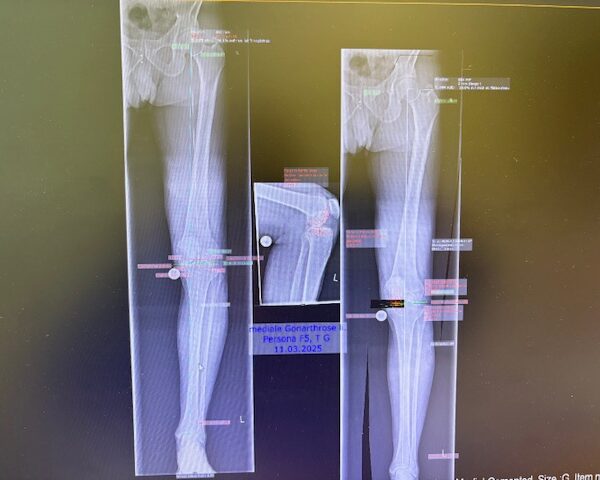

Ο ακτινολογικός έλεγχος (ακτινογραφίες/μαγνητική τομογραφία) ανέδειξε προχωρημένη οστεοαρθρίτιδα του έσω κονδύλου, με πλήρη διατήρηση του έξω διαμερίσματος και της επιγονατιδομηριαίας άρθρωσης. Με βάση αυτά τα ευρήματα, ο ασθενής ήταν ιδανικός υποψήφιος για μερική (μονοκονδυλική) αρθροπλαστική γόνατος.

Πραγματοποιήθηκε απεικόνιση και ψηφιακός σχεδιασμός της επέμβασης, ώστε να προσδιοριστεί με ακρίβεια το μέγεθος και η θέση των προθέσεων. Ο στόχος ήταν να αποκατασταθεί η φυσιολογική μηχανική του γόνατος, διατηρώντας ανέπαφα τα υγιή τμήματα της άρθρωσης, τους συνδέσμους και τους γύρω μυς.